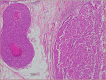

Results: 18 (33.3%) cases were pure EPC, 12 (22.2%) were EPC associated with ductal carcinoma in situ (DCIS) and 24 (44.4%) cases had concurrent invasive ductal carcinoma. EPCs were more likely to present as a solid-cystic mass on sonography (63.8%), regular-shaped (oval or round) (97.9%), lack spiculations (95.7%) and lack suspicious microcalcifications (95.6%). Median tumour size was largest in the EPC with IDC group (18.5 mm). 2 patients developed loco-regional recurrence. Overall survival is good for EPCs of all subtypes.